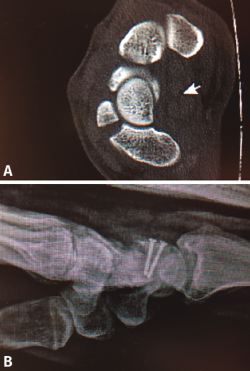

Figura 12. Pequeño fragmento polar superior.

A pesar de todo esto, existen situaciones clínicas específicas que pueden precisar un tratamiento diferente, como pueden ser las fracturas marginales del polo superior del escafoides con preservación del ligamento escafolunar, que pueden tratarse mediante la exéresis del fragmento óseo (Figura 12), o fracturas de pequeño tamaño donde utilizaremos microtornillos no canulados (Figuras 13A y 13B).

Figura 13. Tomografía computarizada donde se evidencia fragmento pequeño y síntesis con 2 microtornillos.